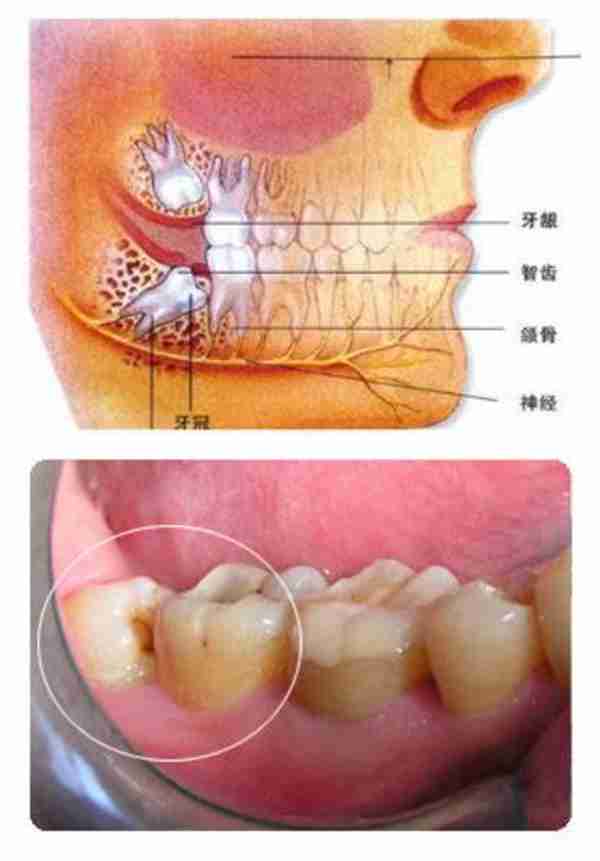

智齿是指人类口腔内牙槽骨上最里面的第三颗磨牙,从正中的门牙往里数刚好是第八颗牙齿。由于它萌出时间很晚,一般在16~25岁间萌出,此时人的生理、心理发育都接近成熟,有智慧到来的象征,因此被俗称为智齿。智齿生长方面,个体有很大差异,通常情况下应该有上下左右对称的4颗牙,有的少于4颗甚至没有,极少数人会多于4颗。萌出的年龄差异也很大,有的人20岁之前萌出,有人40、50岁才长或者终生不长,这都是正常现象。

牙齿萌出困难称为 阻生齿 或 埋伏牙 。阻生齿最常见于下颌第三磨牙,俗称智齿,此牙萌出年龄在18岁前后,由于萌出前其它牙齿都早已站好队列了,等智齿生长出来时,就会受到其它牙齿的排挤,故而萌出困难,形成了阻生齿或埋伏牙,我们称之为 阻生智齿 。